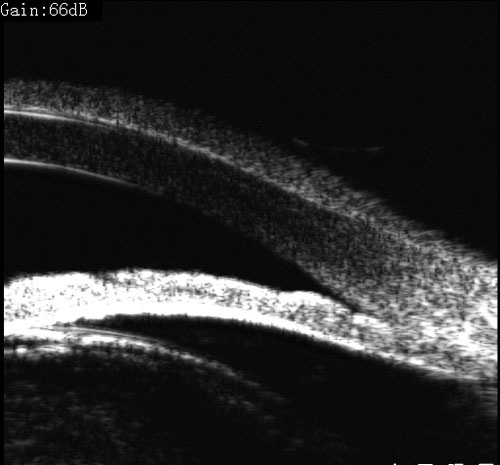

青光眼合并白内障